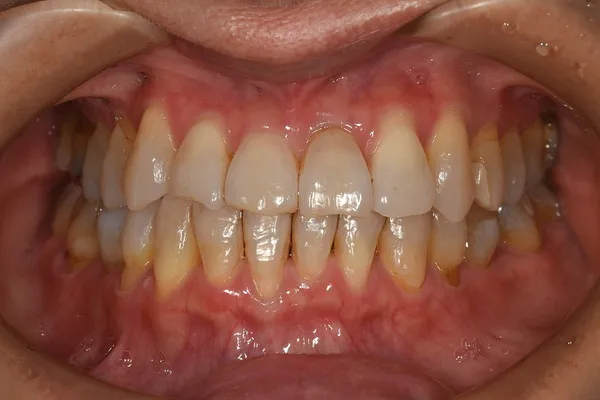

症例

Before

After

| 主な症状 | かみ合わせがおかしい。 |

| 施術内容 | 右側の臼歯が上下反対に咬合していた。上顎の横幅が小さかったため、固定式の拡大装置を使用し、上顎の横幅を広げて、咬合を改善させた。その後、乳歯から永久歯列への交換と、噛み合わせの経過を見守りながら、口腔筋機能訓練を指導した。 |

| 矯正装置 | インビザライン |

| 治療期間 | 2年8か月 |

| 費用 | 診断料込みで99万円(税込)(診断料38,500円+矯正治療951,500円) |